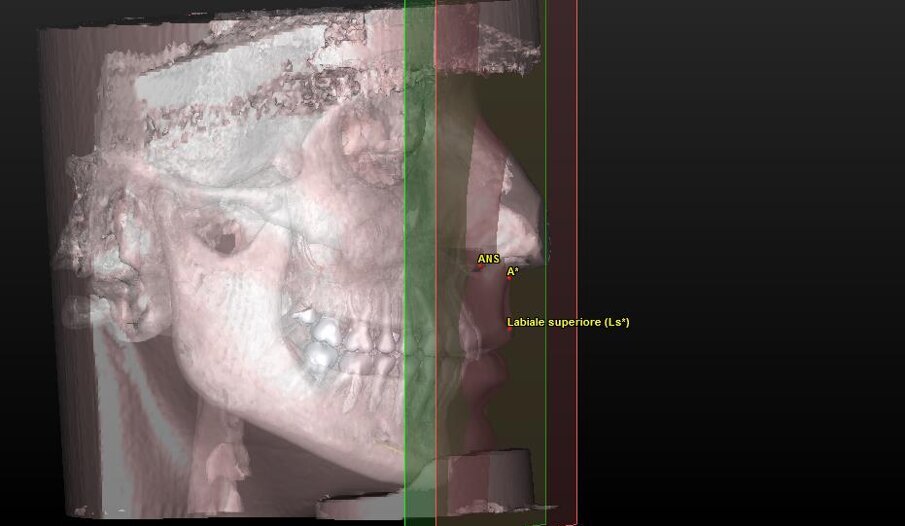

5 landmark per la valutazione estetica dei tessuti molli (Tab. 2) (Fig. 4).

| Ls (Labiale superiore) |

Punto mediano più sporgente anteriormente del vermiglio labiale superiore. |

| A* |

Punto cutaneo del corrispondente punto subspinale A. |

Componente tessuto molle (Tab. 5) (Figg. 10a-11):

ig. 4_Ricostruzione 3D dei tessuti molli del paziente con visione dei landmark utilizzati.

Fig. 10a_Valutazione dei tessuti molli: angolo naso-labiale.